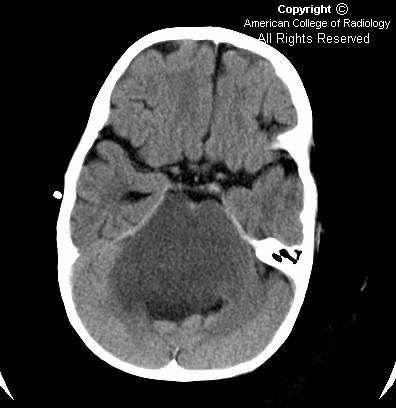

Congenital Cytomegalovirus infection

Findings

Figures 1 and 2: Ultrasound images demonstrate multiple echogenic foci in a periventricular distribution. There is no hydrocephalus or evidence of callosal agenesis.

Figures 3, 4 and 5: Axial CT images show high attenuation within the subependymal region, consistent with calcifications.